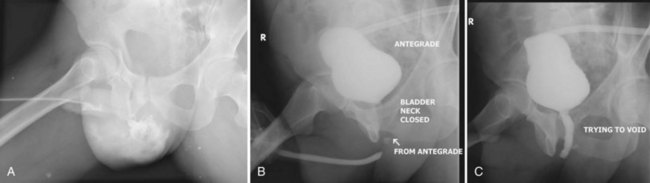

Before the reconstructive procedure is planned, imaging studies are necessary to delineate the characteristics of the urethral rupture defect. A cystogram and retrograde urethrogram should be obtained simultaneously (“up-and-down-o-gram,” Fig. 88–18). The patient is asked to attempt to void with the bladder filled. Ideally, the prostatic urethra should be visualized as the bladder neck opens, enabling measurement of the distance between the severed urethral ends. Should the bladder neck not open, flexible endoscopy should be used to supplement radiographic imaging (Mundy, 1997). The appearance of the bladder neck on preoperative imaging, either open or closed, does not correlate well with bladder neck behavior postoperatively (Mundy, 1997), thus making it difficult to predict bladder neck incompetence or obstruction. MRI has been used successfully to define defect length and to determine the extent and direction of urethral dislocation (Dixon et al, 1992) and the extent of prostatic displacement, and it may help in planning the surgical approach (Koraitim and Reda, 2007).

Figure 88–20 A, Extravasation of contrast medium seen in scrotum on retrograde urethrogram in a patient with a straddle injury. B, Retrograde and antegrade urethrogram shows distal limit of urethral patency, but bladder neck does not open. C, Repeat antegrade urogram study showing proximal limit of urethral patency.